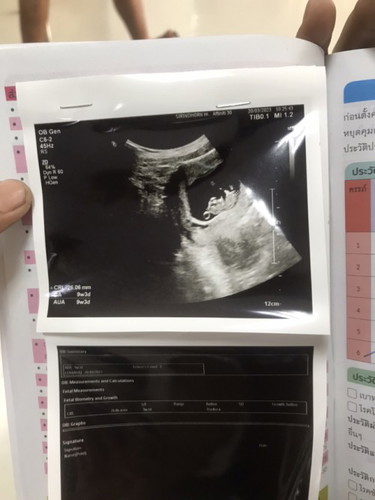

9w6d ถุงกลมๆเหมือนฟองๆคืออะไรหรอค่ะ

ไม่มีอาการแพ้เลย ท้องเเรก 🤏🏻☺️ แต่ว่ามีซีสด้วย จะเป็นอะไรไหมค่ะ เเต่ตอนนี้ซีสเล็กมากยังไม่ใหญ่ค่ะ ถุงกลมๆเหมือนฟองคืออะไรหรอค่ะ

ถุงไข่แดงของน้อง เป็นถุงอาหารเค้าค่ะ สักพักจะเริ่มใ่อ แล้วน้องจะรับอาหารผ่านทางรกแม่แทนค่ะ

กลมๆเล็กๆน่าจะถุงไข่แดงน้องค่ะแม่ ของบ้านนี้ก็มี